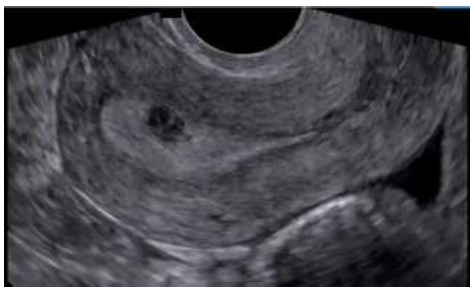

Algumas massas anexiais observadas durante avaliação transvaginal, podem simular uma gravidez ectópica, elas são:

Provas